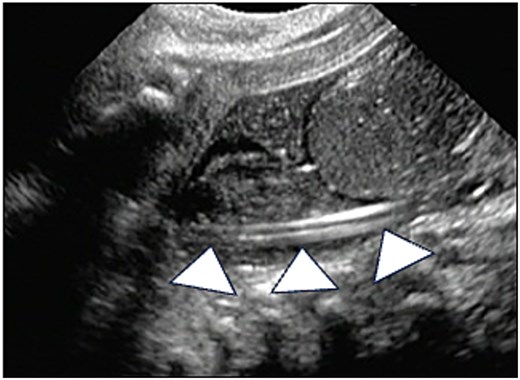

Abdominal ultrasonography. Abdominal ultrasonography showing that the catheter is positioned within the rectum (arrowheads).